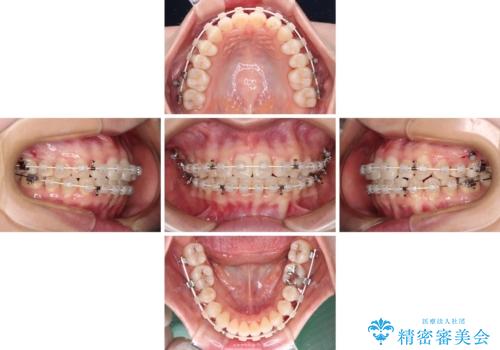

抜歯矯正へ切り替え 表側のワイヤー矯正

上下前歯が非接触である開咬は、インビザラインによる治療がお勧めではありますが、非抜歯矯正か抜歯矯正か悩む口元であり、途中抜歯矯正に切り替えたときに対応しやすいよう、ワイヤー装置にて治療を行うこととしました。

舌の突出癖の影響もあり、非抜歯矯正で治療開始したものの口元が突出し、唇が閉じにくくなってしまったため、途中で第一小臼歯4本を抜歯ししました。